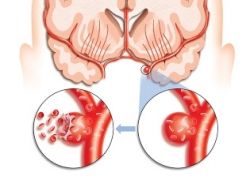

Наш организм постоянно создает вибраторные звуки – биение сердца, перекачивание крови, сокращение мышц, движение суставов. Обычно человек их не слышит, так как они сливаются со звуками окружающего мира. Но в определенных случаях, вибрация ощущается как шум, звон в голове, ушах – тинитус. Сам по себе он является не заболеванием, а его симптомом. Пациенты описывают то, что они слышат как рев, гул, звон, писк, жужжание.